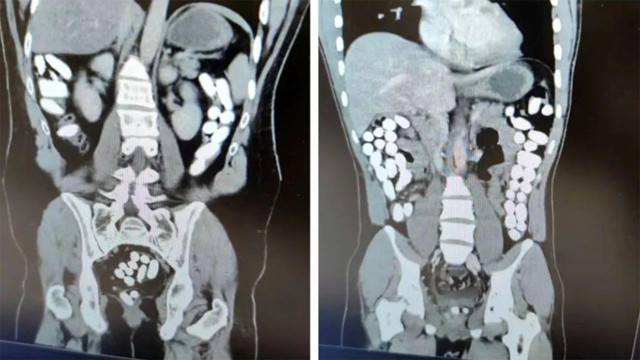

Abone olİl Emniyet Müdürlüğü Narkotik Suçlarla Mücadele Şube Müdürlüğü ile Kaçakçılık ve Organize Suçlarla Mücadele Şube Müdürlüğü ekiplerince yapılan çalışmada; Uygulama noktasında durdurulan yolcu otobüsünde yolcu olarak bulunan İran uyruklu A.G. (25) ve E.P. (21) İsimli şahıslara alınan karara istinaden yapılan tomografi çekiminde mide ve bağırsak kısmında uyuşturucu olabileceğini değerlendirilen çokça yabancı cismin olduğu görüldü.

Yapılan tetkikler neticesinde A.G. (25) isimli şahıstan 100 parça halinde 847,64 gr gelen Afyon Sakızı, E.P. (21) isimli şahıstan 142 parça halinde 1071,80 gr gelen Afyon Sakızı ele geçirildi.